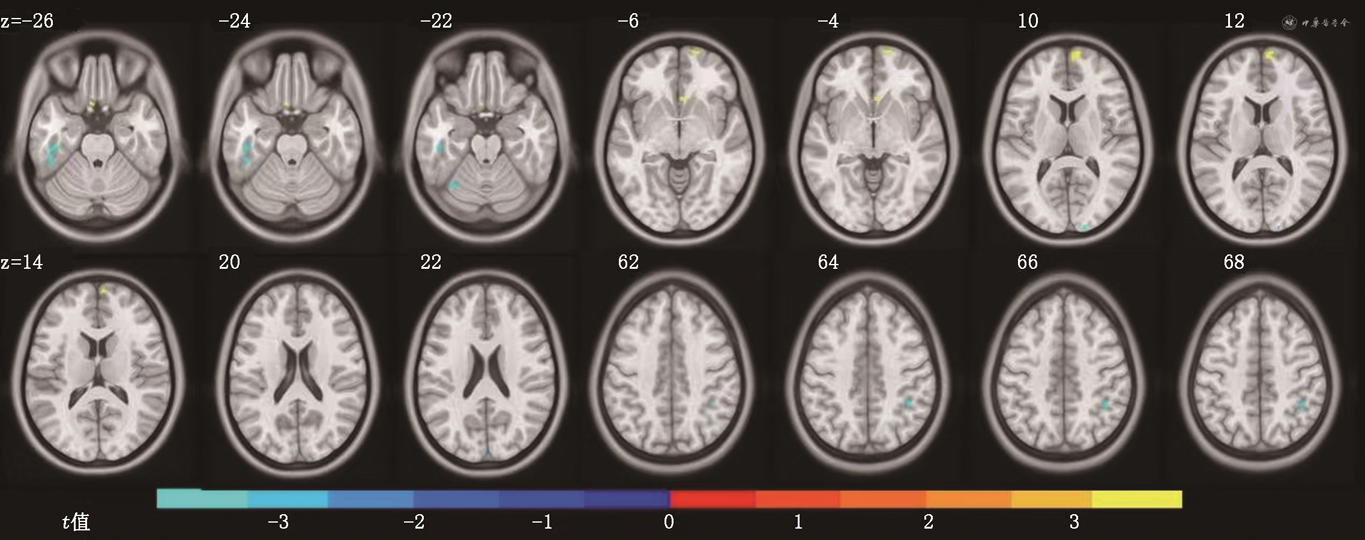

2.基于VBM分析的脑灰质体积比较:见图2及表1。与健康对照组相比,CLP组左侧颞下回、右顶下缘角回、左小脑上部灰质体积均显著减少(P<0.05),右内侧额上回体积显著增加(P<0.05)。

注:浅蓝及蓝色脑区表示与健康对照组相比,伴发腭裂言语障碍的唇腭裂组(CLP组)灰质显著萎缩的脑区;红-黄色表示与健康对照组相比,CLP组脑区的灰质体积异常增加;z为统计变量峰值对应体素的蒙特利尔神经研究所152空间坐标值

两组受试者VBM分析结果灰质体积差异显著的脑区分布

| 团块编号 | 脑区侧别 | 团块大小 | MNI坐标 | 团块水平 t值 | 团块水平 P值 | 解剖脑区 | ||

|---|---|---|---|---|---|---|---|---|

| x | y | z | ||||||

| 1 | 左 | 120 | -48.0 | -36.0 | -27.0 | -3.98a | <0.001 | 颞下回 |

| 2 | 右 | 63 | 40.5 | -48.0 | 46.5 | -3.89a | <0.001 | 顶下缘角回 |

| 3 | 左 | 48 | -31.5 | -64.5 | -21.0 | -3.73a | <0.001 | 小脑上部 |

| 4 | 右 | 30 | 16.5 | -100.5 | 9.0 | -3.67a | <0.001 | 楔叶 |

| 5 | 左 | 22 | -1.5 | -91.5 | 21.0 | -3.51a | <0.001 | 楔叶 |

| 6 | 右 | 37 | 15.0 | 69.0 | -4.5 | 3.83b | <0.001 | 眶部额上回 |

| 7 | 左 | 20 | -6.0 | 16.5 | -24.0 | 3.72b | <0.001 | 回直肌 |

| 8 | 右 | 27 | 4.5 | 22.5 | -6.0 | 3.67b | <0.001 | 嗅皮质 |

| 9 | 右 | 88 | 9.0 | 69.0 | 10.5 | 3.60b | <0.001 | 内侧额上回 |

注:VBM为基于体素的形态学测量;MNI为蒙特利尔神经研究所;a为与健康对照(HC)组相比,伴发腭裂言语障碍的唇腭裂(CLP)组灰质体积显著萎缩(P<0.05);b为与HC组相比,CLP组灰质体积显著增加(P<0.05)